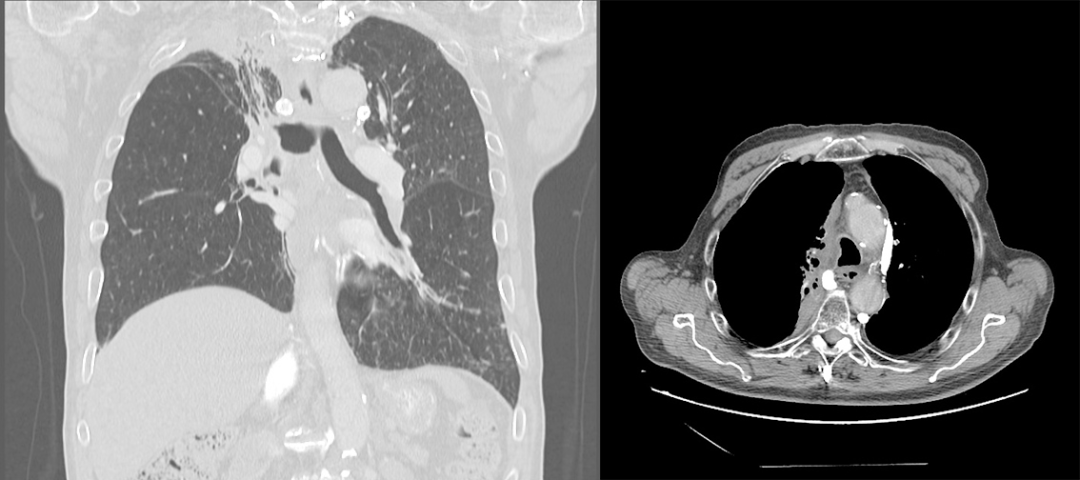

肺不张影像基本思路

2,反s征 / 横s征tum(tumor)肿瘤肿块,atl(atelectasis)肺不张③ 阻塞